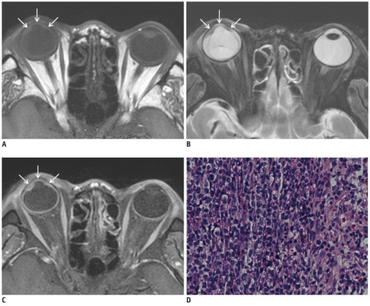

a-c)Posttransplantation intraocular lymphoma- MR images showing smooth, undulating soft-tissue lesion in iris and anterior chamber d)photomicrograph consistent with diffuse large B-cell lymphoma